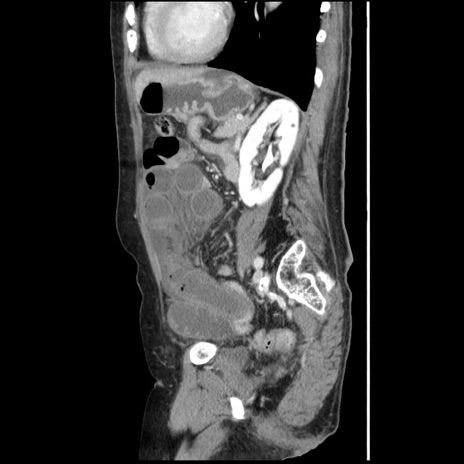

症例1(矢状断像)

【症例】80歳代女性

【主訴】腹痛

【現病歴】8時間前から腹痛あり来院。

【既往歴】糖尿病、脂質異常症、子宮体癌にて子宮全摘術

【身体所見】意識清明・会話良好だが腹痛で苦悶様、全腹部にわたって反跳痛と圧痛あり

【データ】WBC 13600、CRP 0.14、LDH 224、CK 90